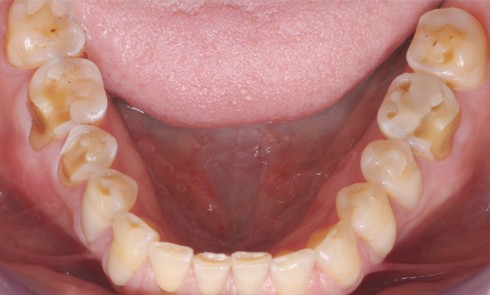

Article réservé à nos abonnés Usure dentaire : origines et formes des lésions

L’usure est la détérioration que produit l’usage. Cette manifestation dynamique, cumulative et adaptative existe depuis l’origine de l’Humanité. C’est un...